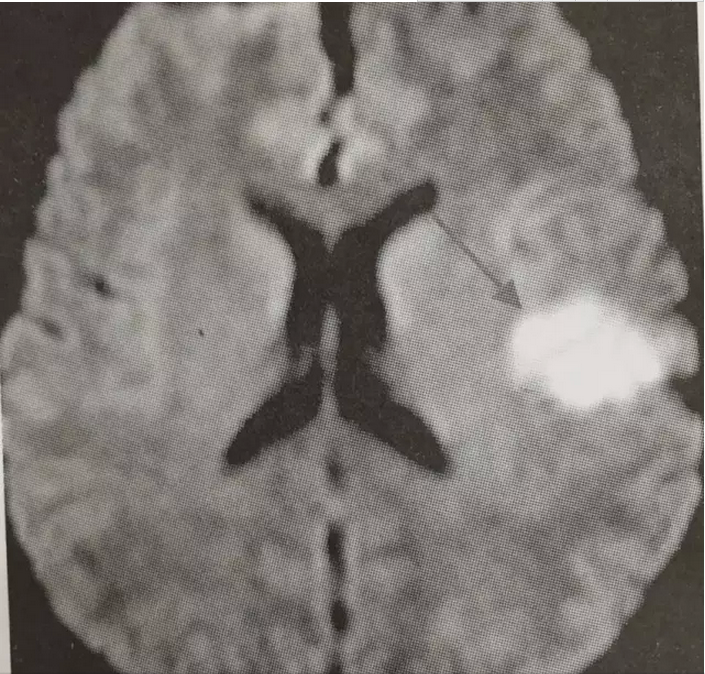

患者为中年女性,反复发生脑梗死,曾就诊于多家医院,考虑过多种临床诊断,包括:(1)患者为中年女性,有高血压病史,反复以脑血管系统受累症状就诊,但短期内既有前循环受累(见图1),又有后循环受累(见图2)的临床表现,且脑血管影像学评估包括超声以及脑血管造影均未见明显为异常。因此不支持脑血管本身病变所致。(2)低血糖症。在外院进行了延时OGTT试验,未发现明显低血糖,同时也进行了自身免疫性因素导致低血糖的筛查,无阳性发现,并且患者发作时表现为非经典低血糖症状(经典的Whipple)三联征:即低血糖症状、发作时血糖降低和供糖后症状迅速缓解),未补充糖症状也可以好转,排除了此种可能。(3)患者为女性,有系统性红斑狼疮家族史,为除外原发性或继发性抗磷脂综合征,入我院后查了LA-SCT(狼疮抗凝物)1.23升高,ANA 1:100,SSA阳性,虽然患者无明显系统受累表现,不能完全除外干燥综合征。但抗磷脂综合征需要3个月内复查抗磷脂抗体,阳性才能确诊。(4)除此之外,该患者临床发作特点为起病急骤、不同次发作累及脑血管不同部位、临床改善迅速,符合脑栓塞表现。但栓子来源于何处?缺血性脑血管病有20%来源于心源性栓塞。因此考虑有无心源性栓塞的可能。本患者虽有高血压病史,但并未发现有阵发或持续心房颤动。进一步于神经内科进行了TCD发泡试验,结果为阳性,提示存在心内秒或心外右向左分流。为进一步明确分流类型,又进行了经食管超声心动图检查及右心声学造影,结果提示存在卵圆孔未闭,且有右向左分流(左心房可见对比剂显影)(见图3)。因此考虑卵圆孔未闭引发的反常栓塞导致脑栓塞可能性最大。因脑栓塞反复发作,故进行了卵圆孔未闭封堵术(见图4)。术后服用阿司匹林100 mg Qd,氯吡格雷75 mg Qd,阿托伐他汀钙片10 mg Qd,随访半年未再发作脑栓塞症状。且复查狼疮抗凝物、抗磷脂抗体、β2-PGI均阴性,不考虑抗抗磷脂综合征,同时患者既往存在的平卧位低氧消失、劳力性低氧症状也消失(既往登山等活动时氧饱和度可降至92%,现一般登山活动无氧饱和度下降)。

图2. 患者第二次脑栓塞MRI示左侧大脑半球梗死(箭头所指)